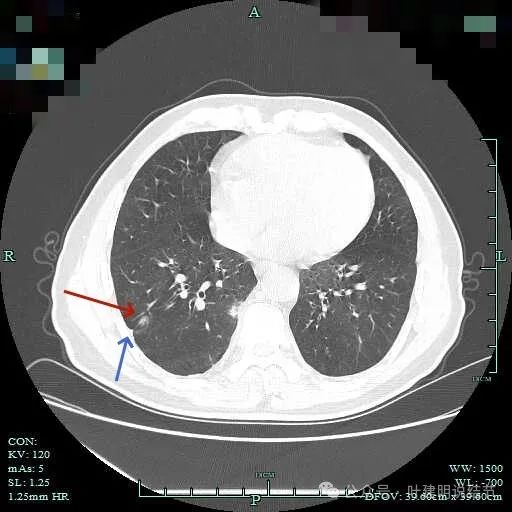

右下脊柱旁怎么也像有磨玻璃结节?但此处正常CT也是略显有慢性炎似的征象的,可这个病人明显结节状,还表面有细毛刺似的。

紧贴脊柱处混合密度,趴在脊柱上,这不像结节状。

但有小血管似的,磨玻璃部分界限较清。但此类异常影像在正常人的CT上也挺常见。